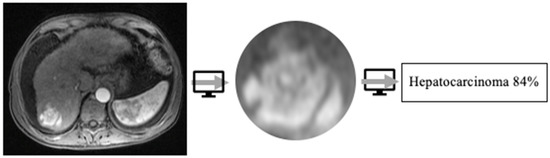

4.3. Classification

- Kim, J.; Min, J.H.; Kim, S.K.; Shin, S.Y.; Lee, M.W. Detection of hepatocellular carcinoma in contrast-enhanced magnetic resonance imaging using deep learning classifier: A multi-center retrospective study. Sci. Rep. 2020, 10, 9458. [Google Scholar] [CrossRef]